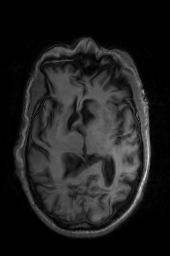

校正偏置场ants.n4_bias_field_correction()

n4_img = ants.n4_bias_field_correction(move_img)

n4_img = ants.from_numpy(np.array(n4_img.numpy(), dtype='uint8'))

n4_img.to_file('TRSAA_n4.png')

'OG' 'OG_n4' 'TRSAA' 'TRSAA_n4'